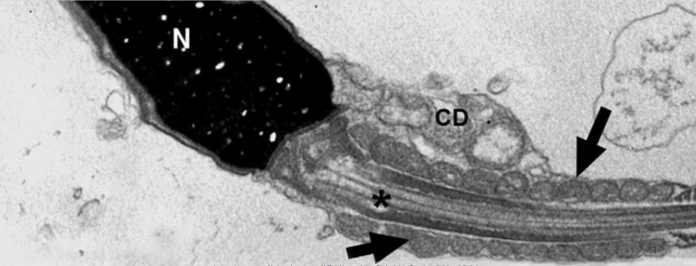

Para preencher essa lacuna de conhecimento científico, o estudo atual, financiado pela Fapesp, lançou mão das tecnologias de PCR em tempo real para detecção de RNA e de microscopia eletrônica de transmissão (TEM) para analisar espermatozoides ejaculados por homens convalescentes de covid-19.

Foram estudadas amostras de sêmen de 13 pacientes infectados e que desenvolveram covid-19 nas formas leve, moderada e grave atendidos no Hospital das Clínicas (HC) da Faculdade de Medicina da USP (FMUSP), com idade entre 21 e 50 anos, em um período de até 90 dias após a alta e 110 dias após o diagnóstico. Apesar de todos terem testado negativo para a presença do sars-cov-2 no teste de PCR do sêmen, o vírus foi identificado em espermatozoides de oito dos 11 (72,7%) pacientes com doença moderada a grave até 90 dias após a alta hospitalar, o que, segundo os autores, não quer dizer que não esteja presente por mais tempo.

O sars-cov-2 também foi identificado em um dos dois pacientes com covid-19 leve. Assim, entre os 13 infectados, nove (69,2%) tiveram sars-cov-2 detectado de forma intracelular nos espermatozoides ejaculados. Outros dois pacientes apresentaram desarranjos ultraestruturais nos gametas semelhantes aos observados nos pacientes em que o vírus foi diagnosticado. Desse modo, os pesquisadores consideram que, ao todo, foram 11 os participantes com a presença viral dentro do gameta masculino.

“Mais do que isso, observamos que os espermatozoides produzem ‘armadilhas extracelulares’ baseadas em DNA nuclear, ou seja, o material genético contido no núcleo se descondensa, as membranas celulares do espermatozoide se rompem e o DNA é expulso de forma extracelular, formando redes semelhantes às descritas anteriormente na resposta inflamatória sistêmica ao sars-cov-2”, relata Jorge Hallak, professor da FMUSP e coordenador do estudo.